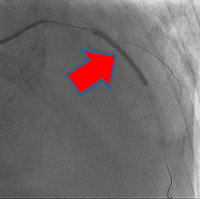

経皮的冠動脈インターベンションの一例

- 【1】術前

- 【2】ワイヤー通過

- 【3】ステント留置

- 【4】術後